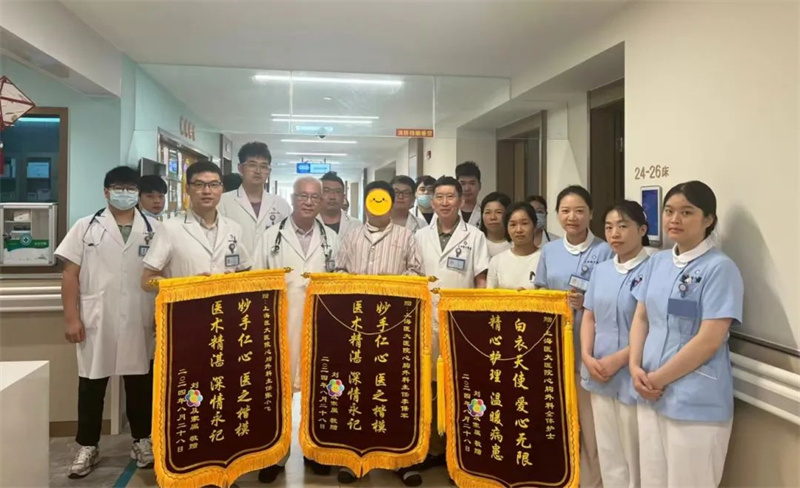

新突破!我院心外科专家团队成功实施高难度“佛罗里达袖”主动脉根部修复术

该患者手术近六个小时,由李保军主任主刀,在团队医师、麻醉医师、体外循环医师、手术护士的全力配合下,术中,除实施主动脉根部 “Florida Sleeve” 修复术,还实施了升主动脉置换术、室间隔缺损修补术、主动脉窦瘤修补术、卵圆孔缝闭术。手术过程非常顺利,术后患者转入监护室,后安全转回心外科病房。

术后,在我院心脏中心医护人员的精心照料下,患者身体逐渐恢复,患者及家属表示对此次手术非常满意,并对我院心外科李保军主任团队的专业技术和无微不至的关怀表示由衷的感激,目前患者恢复良好,已顺利出院。